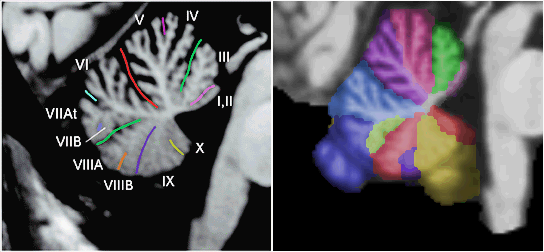

The surface of the brain, or grey matter, is where the functional activation

of the brain occurs and one way of visualizing the activity of the brain

is to create a surface-based map. To do this, one begins by obtaining a

representation of the surface of the cortex. For example, a region of the

brain is isolated in a magnetic resonance imaging (MRI) volume by stripping

away all the undesired regions. For example, the cerebellum can be isolated

by stripping away the scalp, skull, cerebrospinal fluid and cerebrum in

an MRI volume. The cerebellum is located in the

lower left part of the following image. The next image illustrates various

regions which have been color coded for identification purposes.